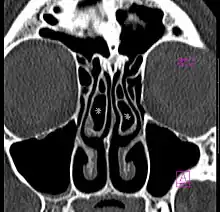

- Large concha bullosa